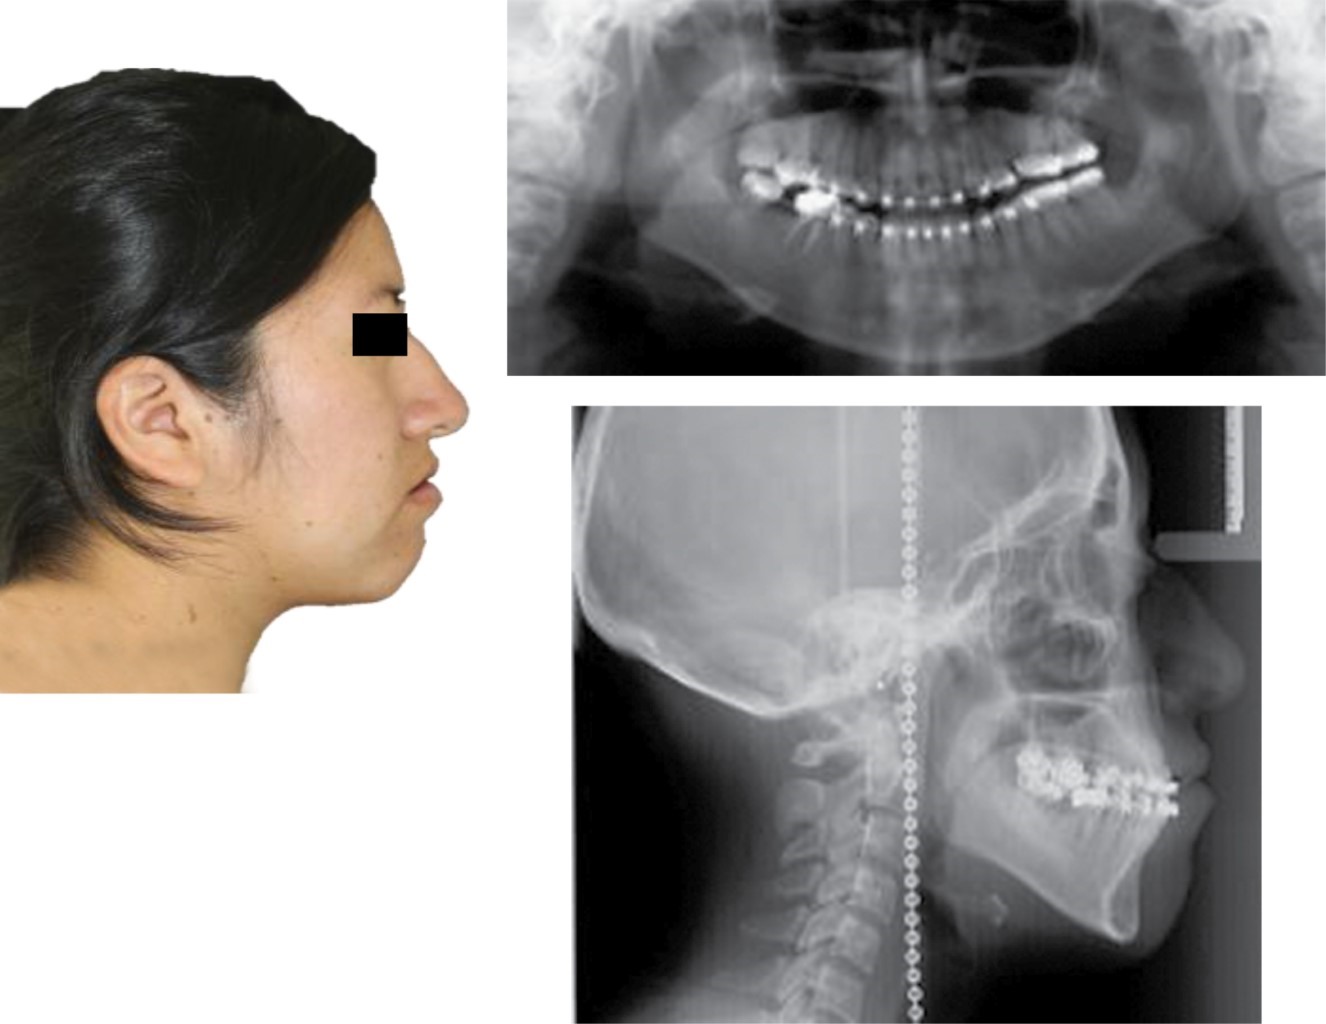

RESULTS

The treatment was completed in 23 months, in which the profile was improved, the gingival smile was eliminated, providing facial harmony (Figure 12). The crossbite was eliminated leaving a more stable case, providing an adequate dental harmony, class I canine, and bilateral molar. It was possible to center the dental midlines, improve the shape of the arches, and vertical and horizontal overbite (Figure 13). The dental inclinations were improved and skeletal class I was achieved (Figure 14). A circumferential retainer was placed to improve the occlusal set. After two months, the occlusal adjustment was performed (Figure 15). The changes obtained can be observed facially (Figure 16), occlusally (Figure 17), and radiographically (Figures 18 and 19).

Figure 12

Figure 13

Figure 14